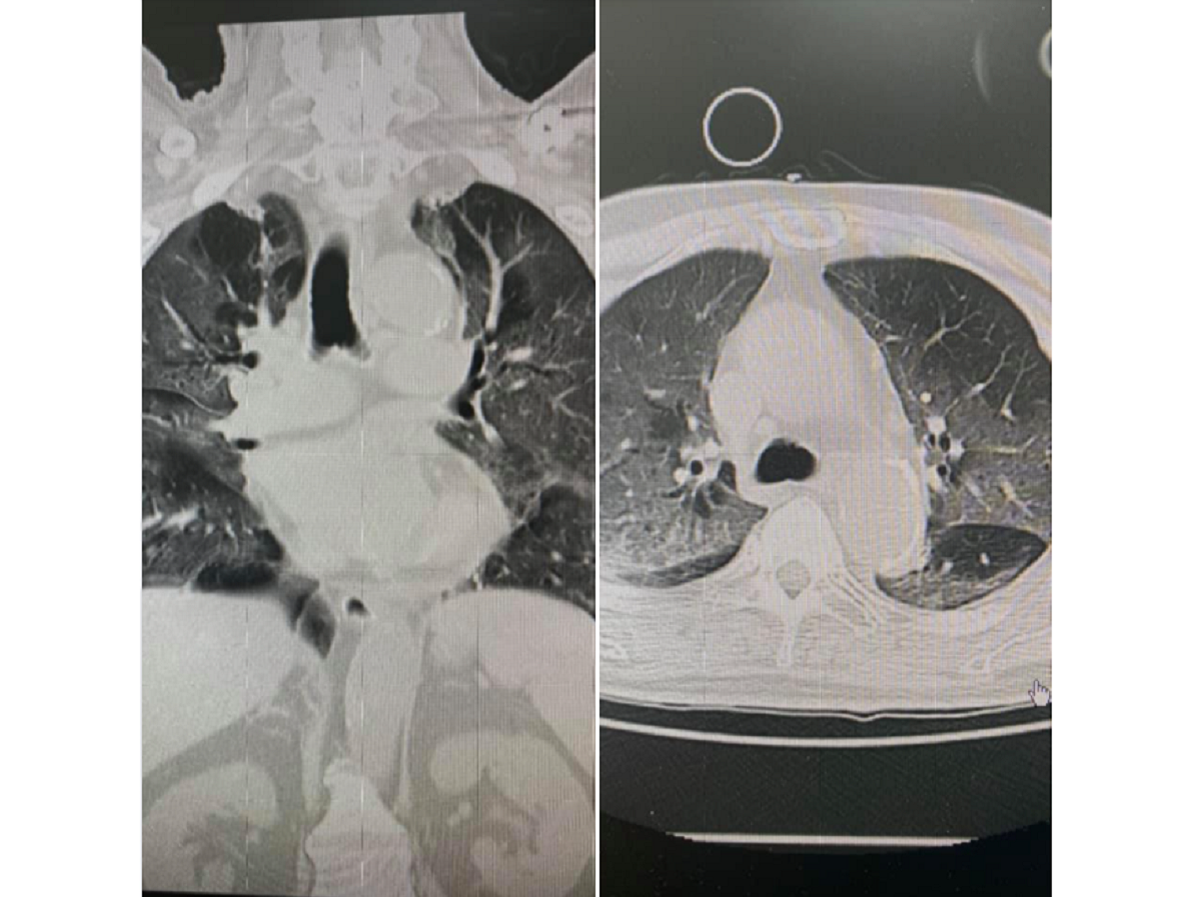

柯世祐發文指出,在強大疫情的攻擊之下,他是悲觀的,「看著前幾個小時,用氧氣鼻導管還可以讓血氧維持94%以上,然後還等不到病床,在急診就惡化到要插管的病人所謂的happy hypoxia(快樂缺氧)真的是COVID -19給病人最後的溫柔啊...在臨死之前,給予病人最後的擁抱,然後就攫取了病人的肺,讓你往死亡走去。」